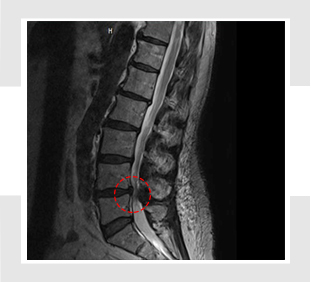

척추관 협착증이란 척추 중앙의 척추관, 신경근관 또는 추간공이 좁아져서 허리의 통증을 유발하거나 다리에 여러 복합적인 신경 증세를 일으키는 질환을 뜻합니다.

척추관이란 척추 가운데 관 모양의 속이 빈 곳으로 아래 위 척추에 의해 추간공이 생기며 가운데 관 속은 뇌로부터 팔다리까지 신경(척수)이 지나가는 통로가 됩니다.

가장 흔한 원인으로 척추 퇴행성 골관절염이 생김에 따라 허리 관절의 크기가 커지고 인대도 두꺼워지는 동시에 가시 같은 뼈가 자라나 신경 길을 좁아지게 만듭니다.